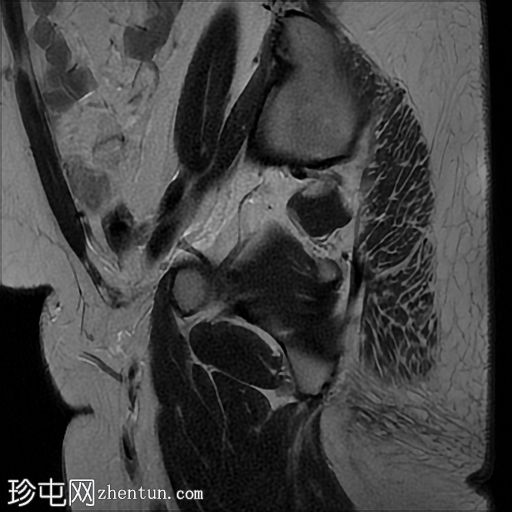

冠状位

T2加权像

左侧卵巢增大,呈弥漫性低T1信号和高T2信号,可见周边卵泡,部分卵泡除周边卵泡周围有环状强化外,无明显实质强化。左侧附件蒂呈漩涡状,提示卵巢扭转。

巨大卵巢水肿是一种罕见疾病,几乎总是单侧发生,且多见于右侧。复发性卵巢部分扭转是其发病机制的主要怀疑因素,可导致静脉和淋巴回流受阻,进而引起卵巢间质肿胀和水肿。